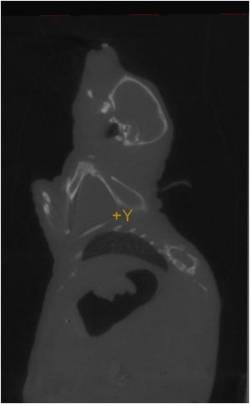

Figure 3. Left and right sagittal CT images of mouse with iodinated liposome injected in left eye vein

Figure 4. Transverse CT image of mouse